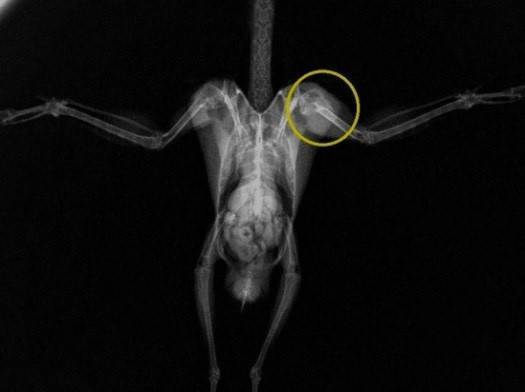

これが治療前のレントゲンです。

左の上腕骨(人でいうと腕の部分)の骨が折れているのがわかります。